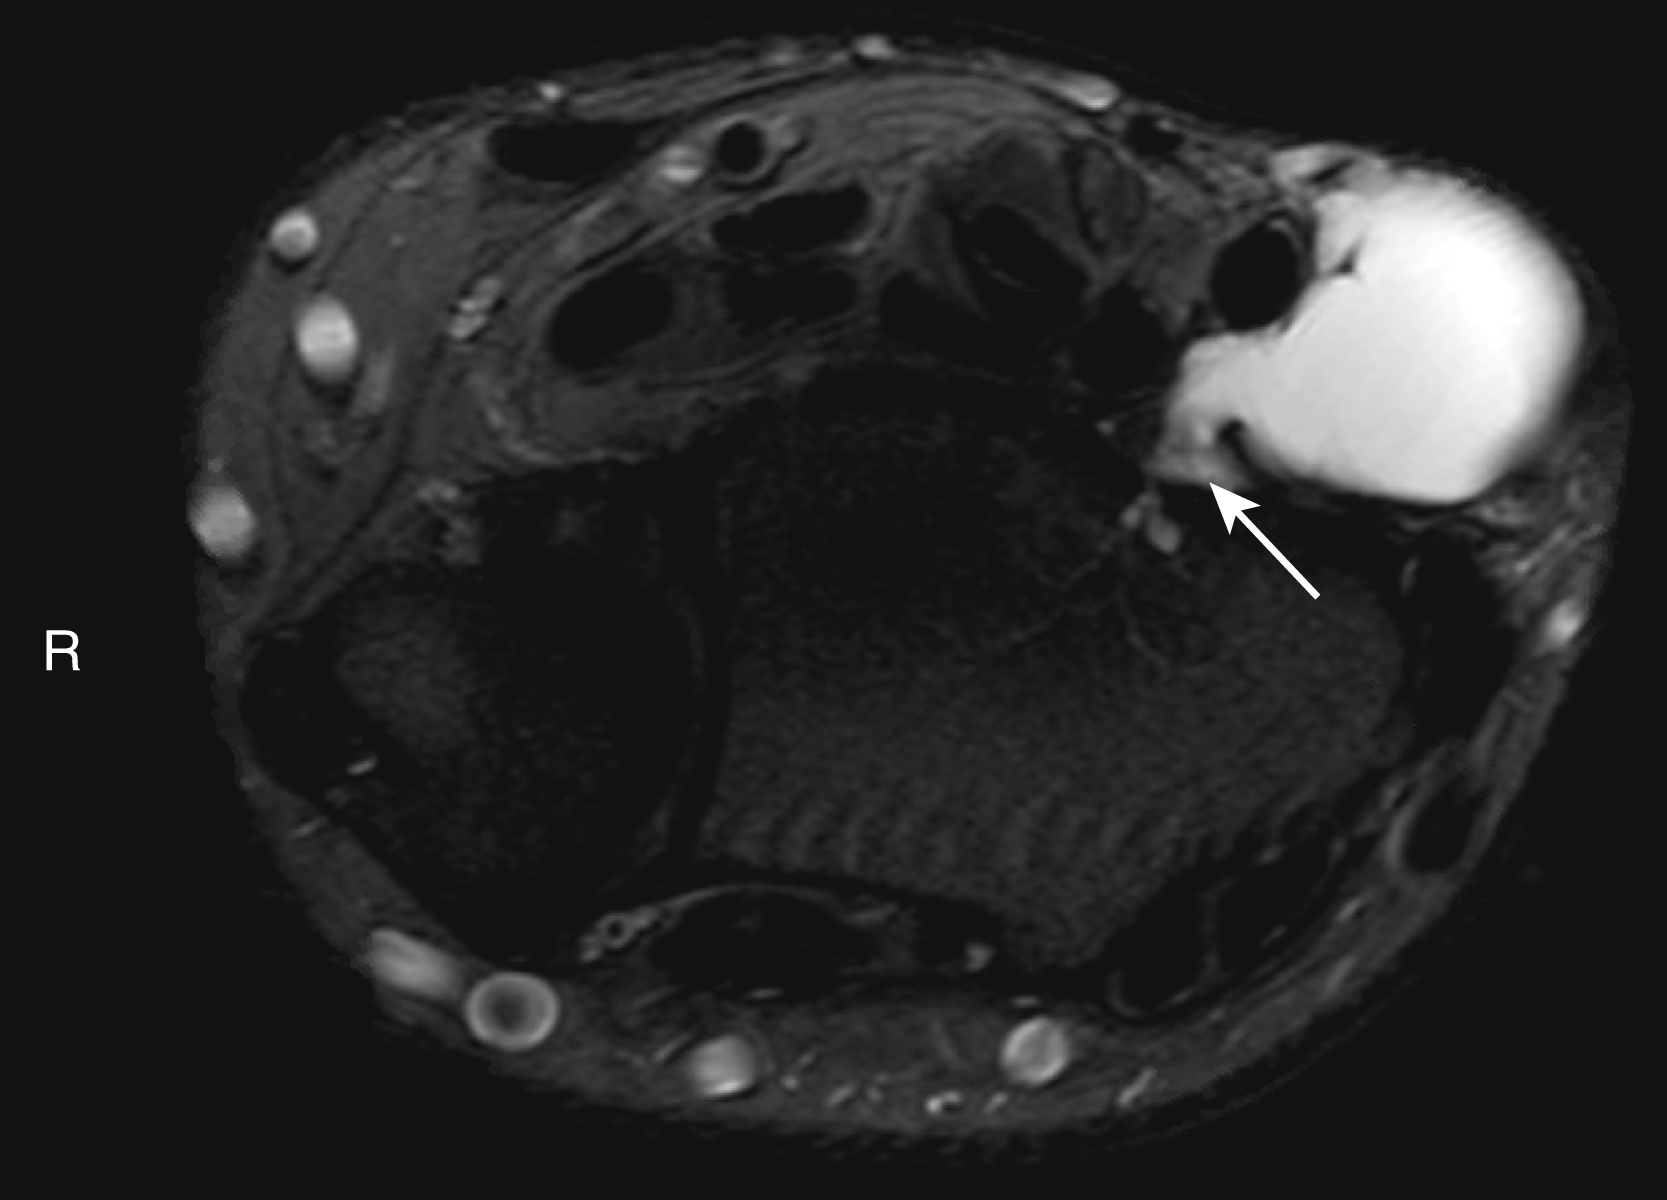

Magnetic resonance imaging (MRI) provides the highest definition of soft tissue lesions and provides the best information regarding soft tissue planes. MRI’s utility is greatest prior to biopsy, as surgical changes will distort borders of the structures. Generally, intravenous contrast is required in order to truly characterize masses; this is especially true in vascular malformations.

The vast majority of wrist ganglions present as atraumatic, slow-growing, painless masses, with over 70% located on the dorsal wrist ( Fig. 60.5 ) and approximately 20% located on the volar wrist. Typically, ganglions are asymptomatic, although dorsal ganglions may cause discomfort when extending the wrist. Patients frequently describe the mass swelling with activity and decreasing in size with rest. On examination ganglion cysts typically are firm, round lesions that transilluminate. Dorsally, ganglion cysts most frequently arise from the scapholunate ligament; volarly they commonly originate from the scaphotrapezium–trapezoid joint. Asymptomatic ganglion cysts require no treatment, however when treatment is indicated, management is through direct surgical excision. Aspiration of the cyst has a high recurrence rate. During surgical excision, it is essential to locate and remove the stalk of the lesion to prevent recurrence; cauterizing the base of the lesion is also recommended to devitalize any microscopic remnants left behind. When treating volar ganglions, care must be taken to avoid the radial artery, as the lesions are frequently intimately associated with the artery ( Fig. 60.6 ). For this reason, we routinely obtain MRI on volar ganglions to assist with surgical planning.